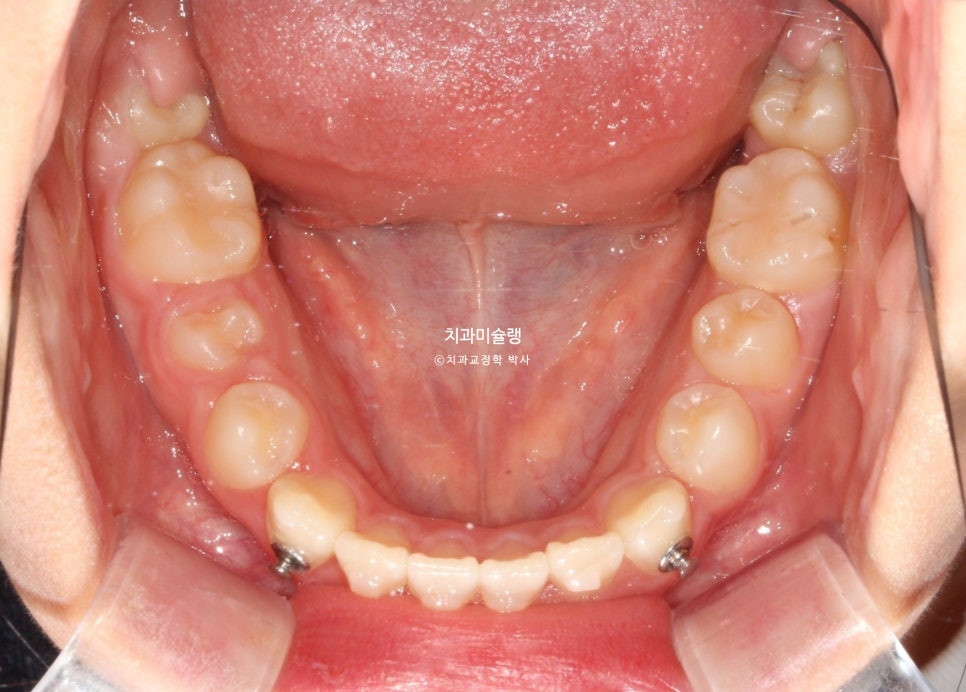

7개월간 36개 장치를 낀 후 모습 입니다.

덧니는 잘 내려왔고 앞니 배열은 양호하나 개방교합과 절단교합이 남아있습니다.

어금니 교합관계 개선을 위한 3급 고무줄을 열심히 끼도록 당부했죠.